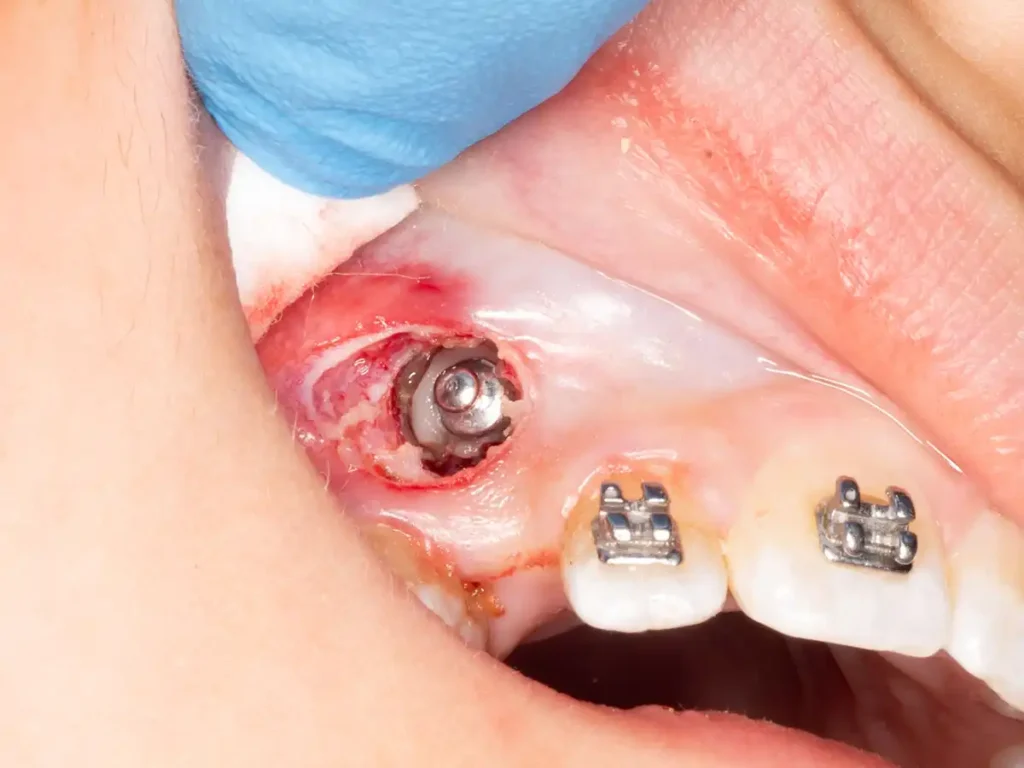

Una vez evaluada la posición y profundidad del canino retenido, se indicó su exposición quirúrgica y la adhesión inmediata del botón de tracción ortodóntica en el mismo acto operatorio. Esta secuencia permite evitar pérdidas de tiempo entre la exposición y el inicio del movimiento dentario.

La apertura quirúrgica se realizó con electrocirugía, permitiendo un campo operatorio limpio y buen control visual. Luego se instaló la mecanoterapia inicial para comenzar la rotación coronaria y orientar el canino hacia una posición más favorable dentro de la arcada.

La duración total de la intervención, incluyendo la fase quirúrgica e instalación de la mecanoterapia inicial, fue de aproximadamente 40 minutos. En el postoperatorio inmediato y mediato el paciente evolucionó favorablemente, sin dolor relevante ni complicaciones quirúrgicas.